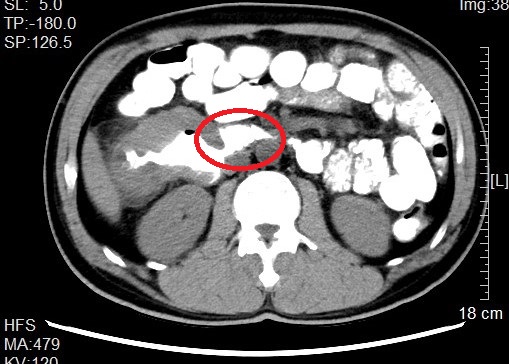

来自省内正值中年的邹先生和张先生都因“阵发性腹痛不适感”就医而发现结肠肿瘤,慕名转诊找到我院治疗。杨春康教授接诊,经过详细全面的检查后,发现二者的病情相似,都为升结肠近肝曲部的肿瘤且肿瘤已侵犯临近的重要脏器——十二指肠,全身其他部位没有发现肿瘤转移病灶,属于局部晚期病例。面对仍有治愈希望的病人以及家属的殷切希望,尽管病情高度复杂,手术风险和压力巨大,杨春康教授和他率领的医疗护理团队没有在困难面前退缩。在与病人及家属充分沟通后,决定为他们手术,并制定周密的手术方案。